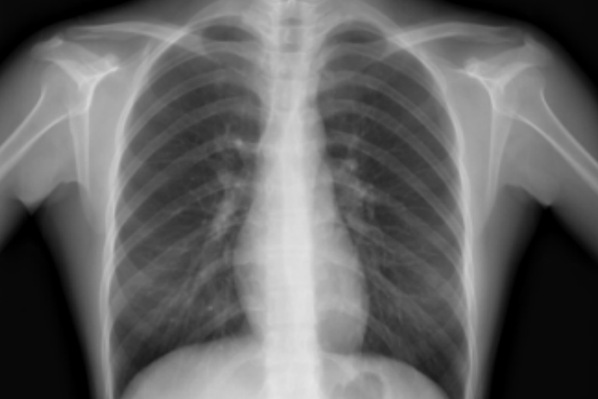

要搞清楚这点,我们先来了解下CT和X线的区别吧。

关于CT和X线,有些朋友们分不大清楚。其实很简单,若把待检查的组织(也就是我们人)比喻成面包,X线就是从前往后压扁了看一块还未切开的面包,在最前面一层隐约可以看见一些内部的情况,但不太清晰。

而CT检查就像是把面包切成片来看,里面每一个小细节都可以准确看出。既然是切面包,则有些面包片会切得更薄一些,我们常说的薄层CT就像是这些更薄的面包片。